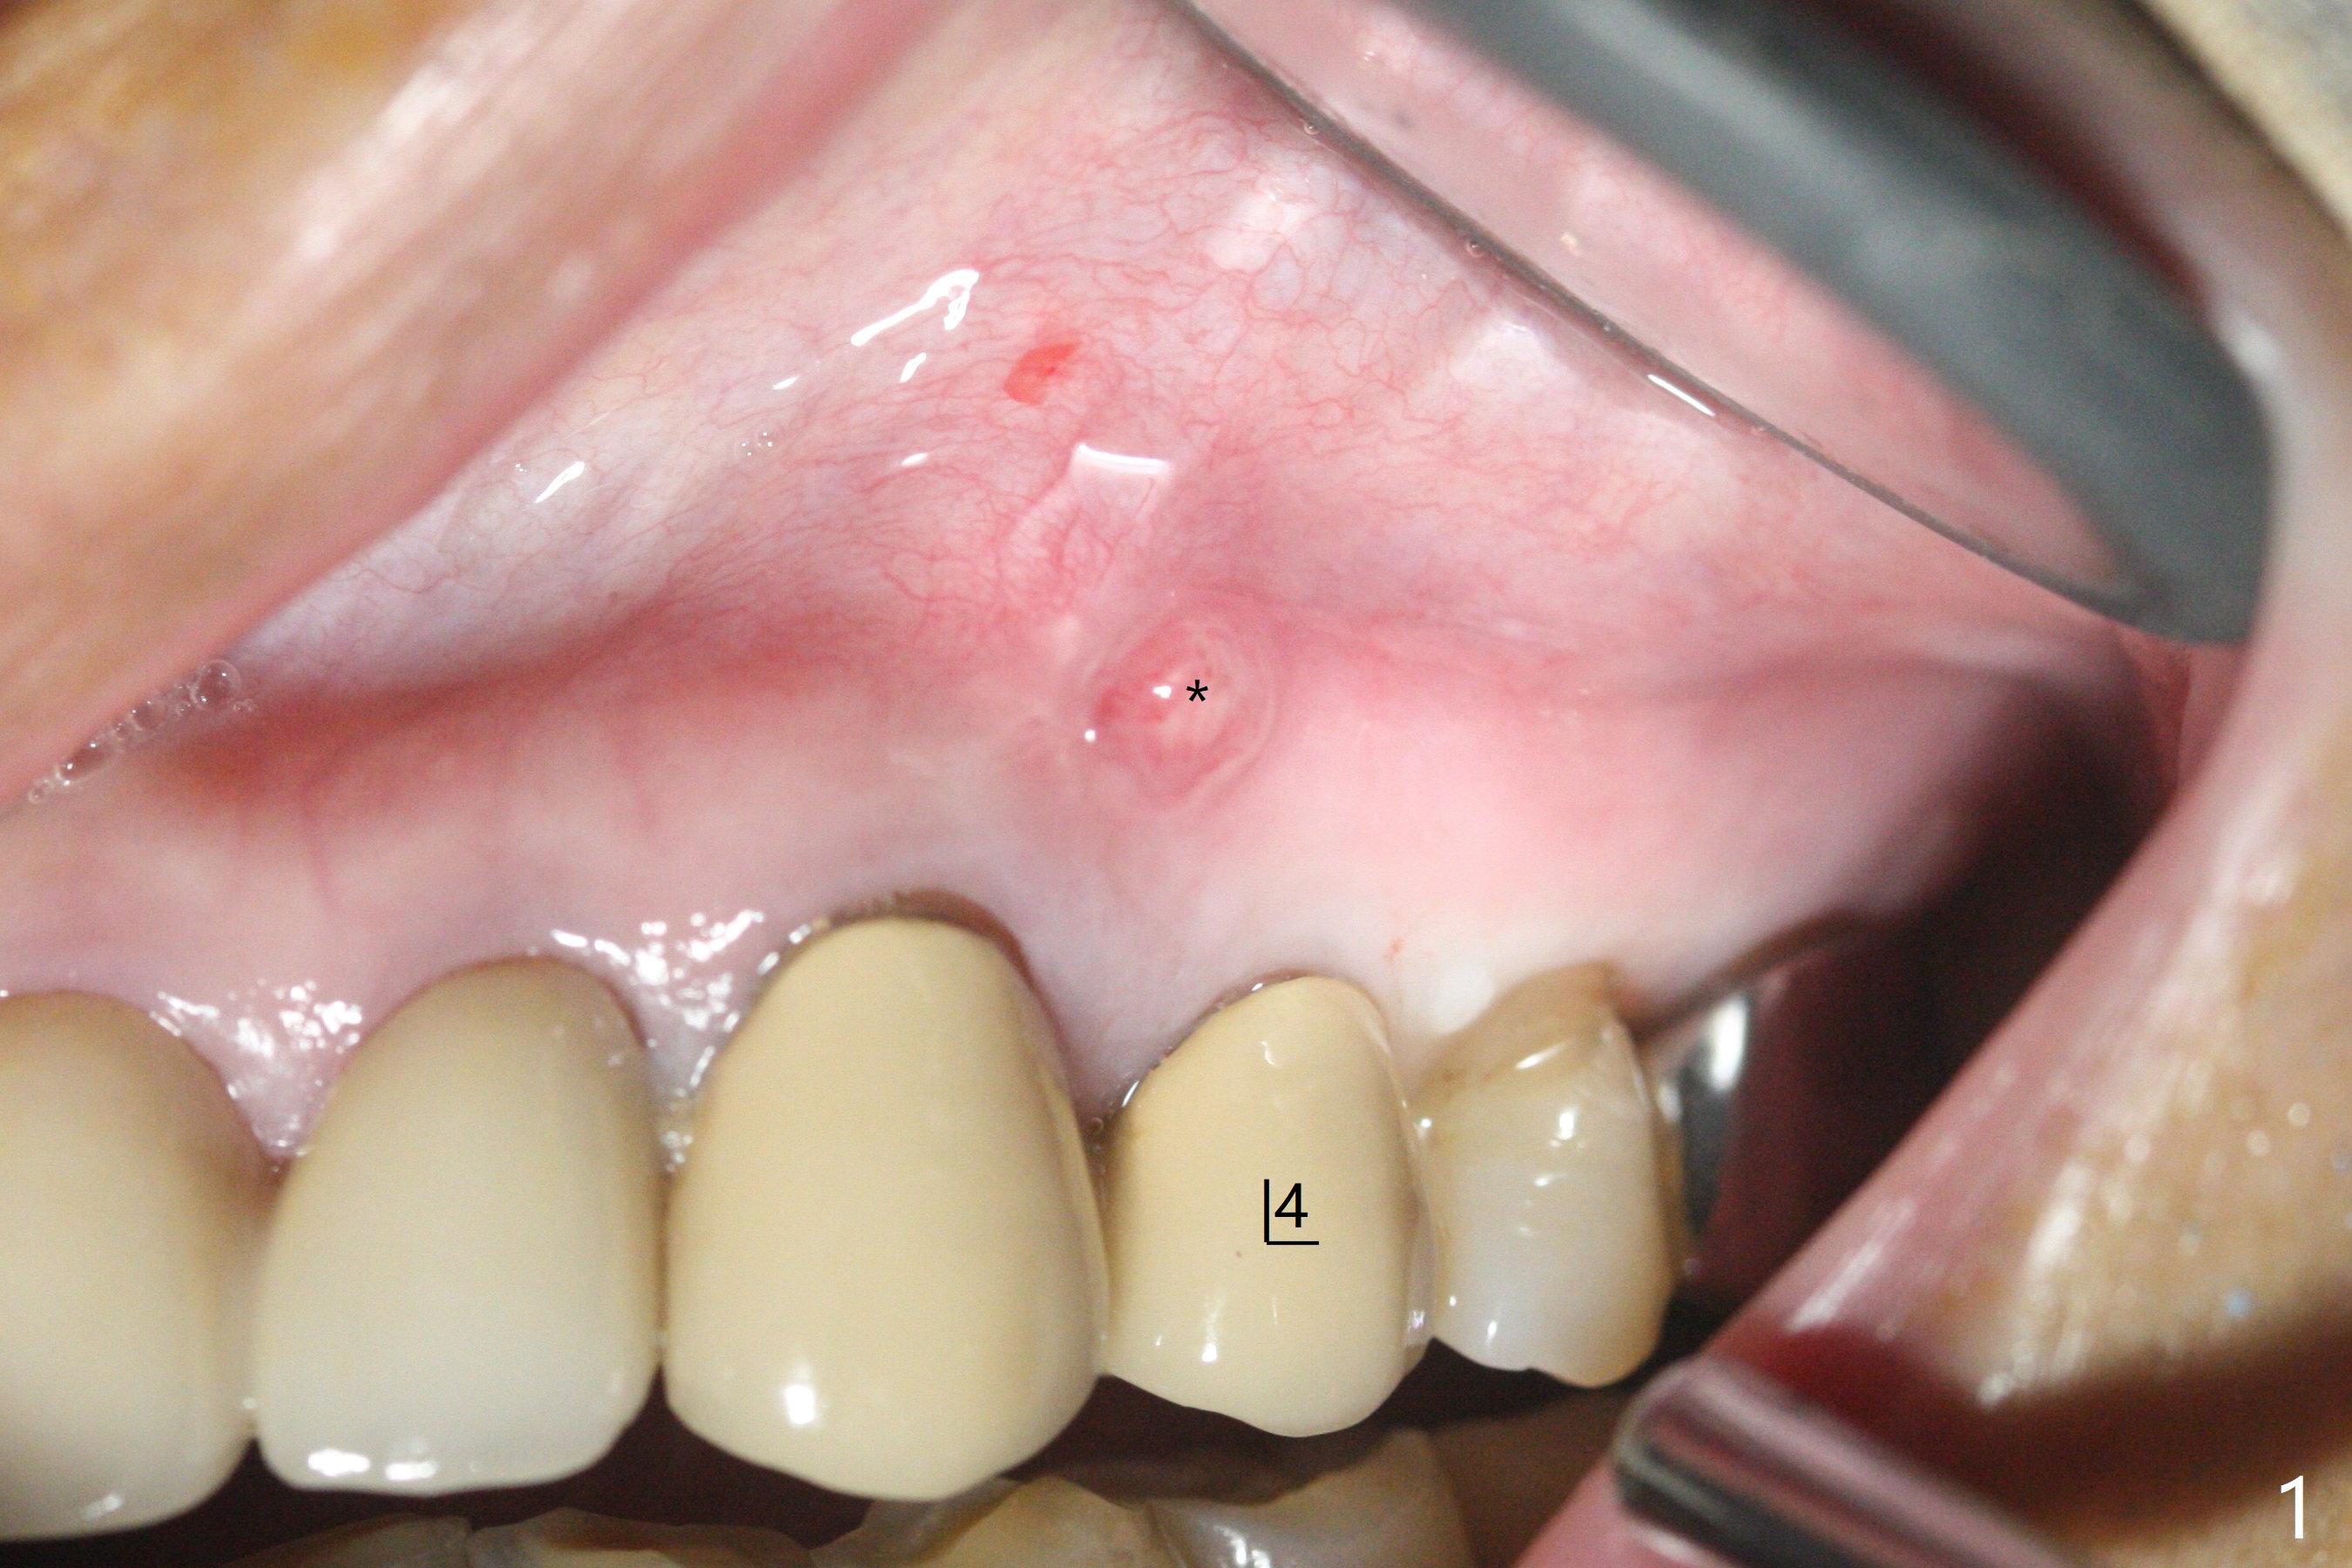

68岁女左上4颊侧瘘道(图一:*),与根尖颊侧骨板缺失相通,其实腭侧根尖周围病变更大(也与颊侧窝相通),术中没有注意腭侧根接近3(图二:P),稀里糊涂的基本顺着腭侧根(颊侧)走向钻洞(图四,与图三理想方向对比),突然记起术前设计钻洞必须在腭侧牙槽窝远中颊侧,在远中建立新洞眼(图五),之后无法再次建立新洞眼,只好利用同一个侧面切割钻头将钻洞往远中移位,同样效果不佳(图六),最后只好放弃,放置粘性骨粉(图七:*),覆盖PRF膜,6个月胶原膜,PGA缝线,牙周胶水。术后重新分析表明顺着腭侧牙槽窝种植与尖牙还是有分离(图八,九:*),因为牙槽窝是斜型的(图十:黑色),不过离颊侧骨板也接近(图八:B)。所以钻洞必须斜型针对远中骨壁,表浅些(图十一:红色箭头);一旦进入骨板,改变角度(图十二:红色箭头),适当矫枉过正,随着植体增大,钻洞会往近中偏移(白色箭头)。最好植体方向理想(图十三)。不过植骨后钻洞偏移可能性比较少。缝线和牙周胶水似乎是一个稳妥固定胶原膜方法。术后病人抱怨水肿严重,术后八天颊侧根尖隆起是由于骨粉推出骨板之外(图十五,十六:*),上颌窦底板无意穿孔(^)伴有上颌窦膜(M)增厚,与术前对比(图十七:上颌窦窦腔清晰)。术后一个月6个月吸收膜不见了,大多数缝线已经脱落,最后两根缝线撤除后,牙槽窝开口已经关闭,好像主要成分是骨粉(图十八)。术后5个月牙槽嵴宽,角化龈也宽,好像可以植入4x11.5毫米植体(图十九)。